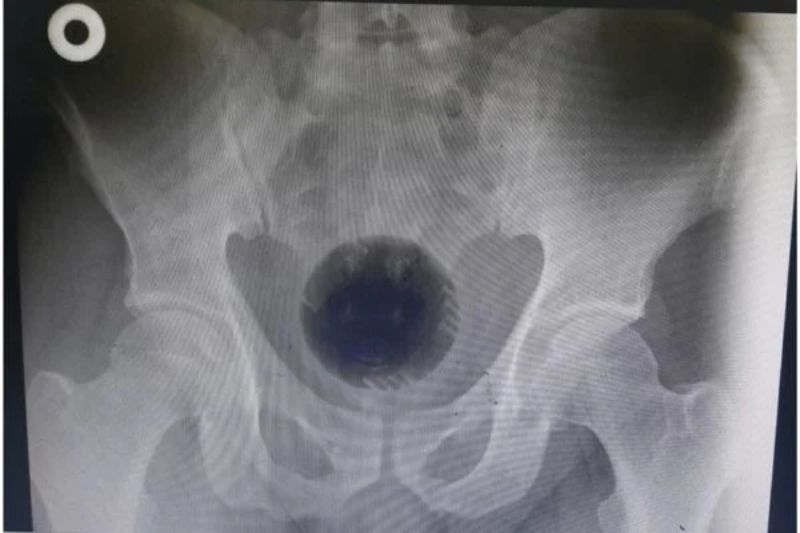

Homem passa por cirurgia para retirar bola de 7 cm presa no ânus

A bola, que fazia parte de um aspirador de pó, ficou presa na pélvis do paciente. Ele contou aos médicos que introduziu o objeto no próprio corpo com a esperança de solucionar um problema de hemorroidas. A equipe relatou, entretanto, não ter encontrado evidências desta condição de saúde.